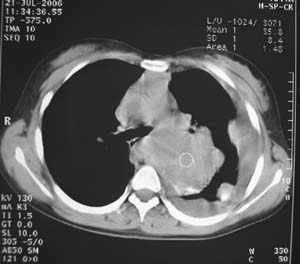

女性,17岁,一年前因股骨病变截肢,现胸憋。

左肺巨大肿块,内散在斑点状高密度骨化影,右肺见多发结节灶,双侧胸膜局限性增厚。有骨肉瘤病史,支持骨肉瘤手术后转移。